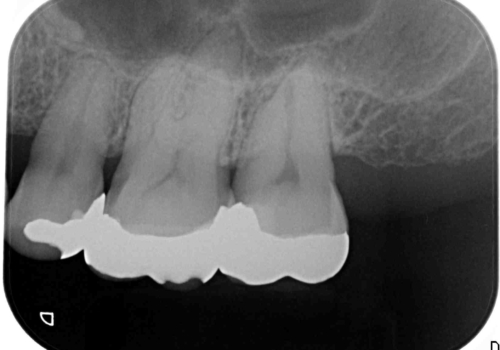

口の中の金属を外したい セラミッククラウンによる治療

- 笑った時に口の中で目立つ金属を外したい、虫歯の治療を再発の内容しっかりと行って欲しいと希望され来院されました。

銀歯・虫歯を丁寧に除去したのち精密なセラミック治療を行うことで長期的な予後を目指します。

銀歯をを外すだけでなく、セラミックを適合よく精密に製作することで長期的な予後を見込むことが可能になります。